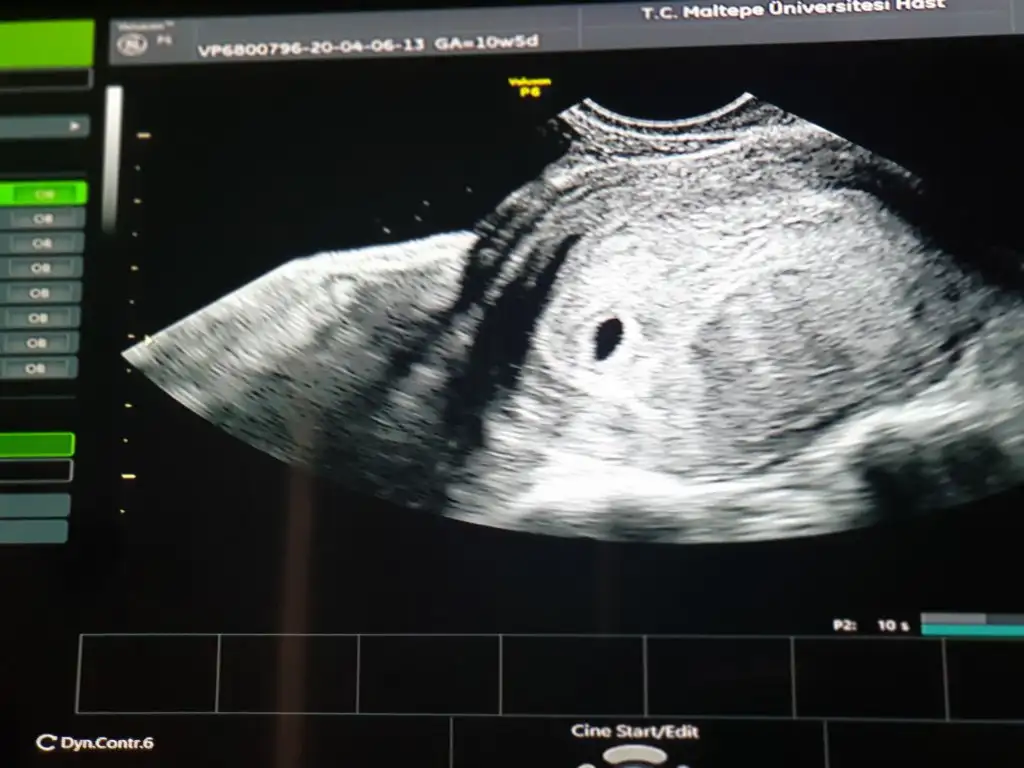

Maşallah canım. Karından mı baktı? Adetin kaç gün geçti? GA=10w5d diyor. Yani 10week5day. Niye öyle yazıyor?

5+3 dedi doktor canım. Karından da görebilirdi belki çünkü beta değerim 3000 i geçmişti. ama ben "4 haftalık saniyorum "diyince göremeyiz dedi hiç bakmadı o yuzde n.Maşallah canım. Karından mı baktı? Adetin kaç gün geçti? GA=10w5d diyor. Yani 10week5day. Niye öyle yazıyor?

Kendi kendime bulduğum bişey. Ultrason kağıdında yazıyor 10w5d yani 10hafta5günlük. Her ultrason kağıdında dikkat ederim. Bilmiyorum belki de doğru değil. Doktoruna sorarsın niye öyle yazıyor diye5+3 dedi doktor canım. Karından da görebilirdi belki çünkü beta değerim 3000 i geçmişti. ama ben "4 haftalık saniyorum "diyince göremeyiz dedi hiç bakmadı o yuzde n.

Benim adet 4 martmıs. Dediğine göre erken yumurtlama olmuş . Ama o 10w olayıni bilmiyorum nedir.

Evet sorarım onu.Kendi kendime bulduğum bişey. Ultrason kağıdında yazıyor 10w5d yani 10hafta5günlük. Her ultrason kağıdında dikkat ederim. Bilmiyorum belki de doğru değil. Doktoruna sorarsın niye öyle yazıyor diye